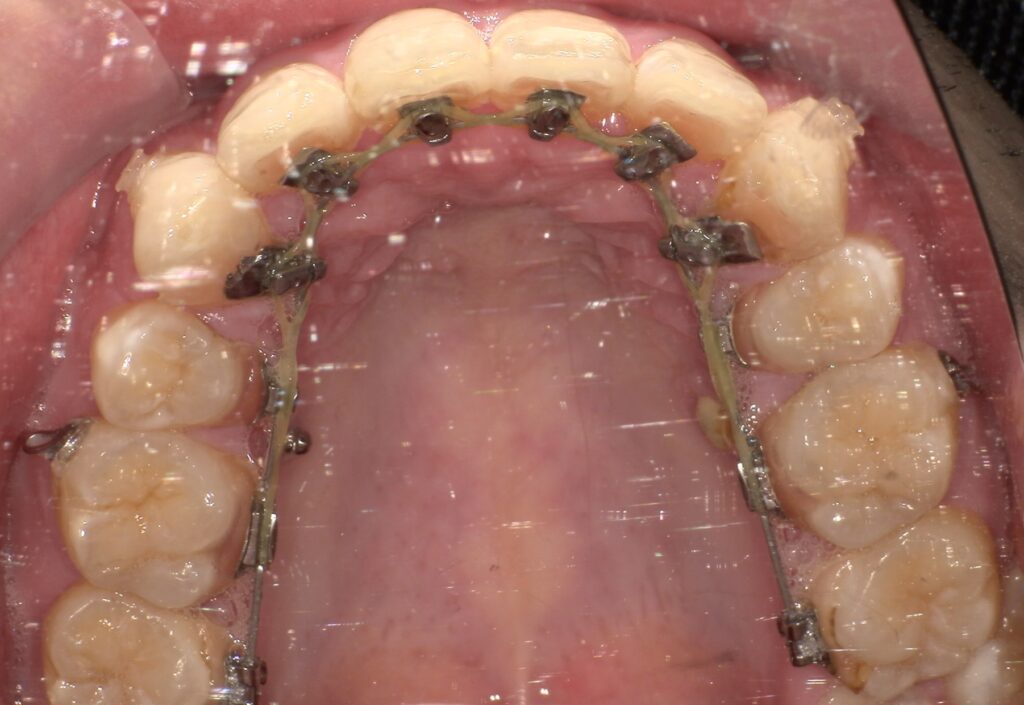

症例紹介

治療前

| 主訴 | 上の歯出てる、口元出てる |

| 診断名 | 上顎前突 |

| 年齢 | 20代男性 |

| 治療内容 | ブラケットを用いたインプラントアンカー2本埋入 |

| 抜歯非抜歯 | 抜歯あり 上44下55EXT |

| 期間 | 動的治療25ヶ月 |

| 費用 | 総額1,364,000(税込) |

| リスク、副作用 | 歯痛、虫歯、歯周病、口内炎、発音障害、歯根吸収、歯肉退縮、歯髄炎、顎関節症、歯の咬耗、エナメルクラック |